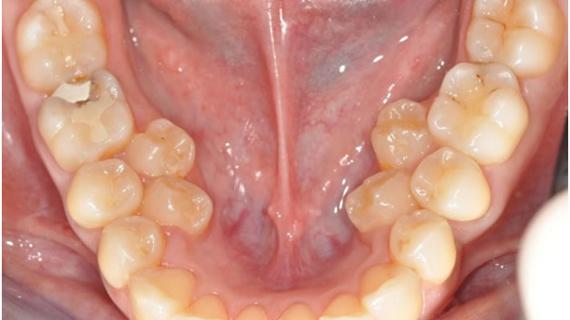

Пульпиты временных зубов в практике детского врача стоматолога: актуальность проблемы, особенности клиники и лечения

Распространенность пульпитов. Временные зубы играют важную роль в жизни растущего организма ребенка. Они оказывают влияние на развитие...